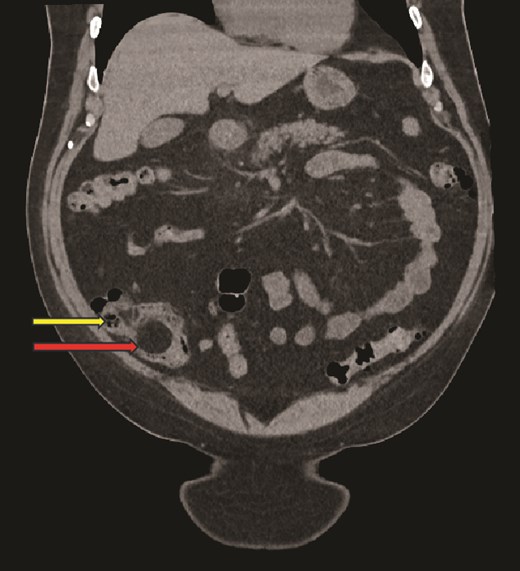

Computed tomography (CT) scan abdomen and pelvis was reported as follows: ‘Inflammatory phlegmon, fat stranding, free fluid, and reactive lymphadenopathy in the right iliac fossa. At the centre of the inflammatory phlegmon there is a dilated appendix with thickened walls. Small appendicolith at the base. Incidental note of a 3.2 cm caecal lipoma, which resides just below the ileocecal valve.’ (Figs 1–3).

Sagittal CT image, showing caecal lipoma (right arrow) and appendicitis (left arrow).